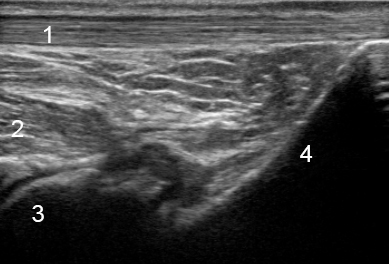

Image - Cheville postérieure : Coupe longitudinale

1. Tendon calcanéen

2. Tendon du long fléchisseur de l'hallux (LFH)

3. Talus

4. Calcanéus